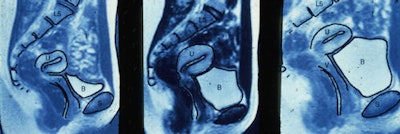

The experiments relied on couples being able to perform under highly technological conditions. Couples had sexual intercourse in the MRI tube after the table had been removed. Images of the pelvis were taken with the woman on her back alone, then in face-to-face coitus. After the man left, the woman was asked to "autostimulate" to achieve orgasm. Images were taken at preorgasm and at 20 minutes after orgasm.

Researchers who conducted an experiment in 1960, using mechanical imitation of natural coitus, noted that during female sexual arousal there was a backward and upward movement of the anterior vaginal wall (vaginal tenting) and a 50% to 100% greater volume of the uterus. The researchers presumed that the greater volume of the uterus was due to engorgement with blood.

"They taught this to us in medical school, but it is nonsense because this was caused by the bladder," van Andel said. "Every woman knows they have to pee after making love ... it is possibly associated with survival value in that a woman needs to urinate as quickly and as much as possible after sex to flush away eventual pathogenic micro-organisms. This is less important for a man who has a longer tube [urethra] and, therefore, has less threat from pathogens."

The researchers also reported that their images showed upward displacement of the uterus and lengthening of the anterior vaginal wall but hardly any change in the position of the uterus during sexual arousal, unless it was caused by insertion of the penis.

"There is value in this for gynecologists," van Andel remarked. "The images will help gynecologists conduct vaginal examinations with more accuracy and with less discomfort or pain to the patient."